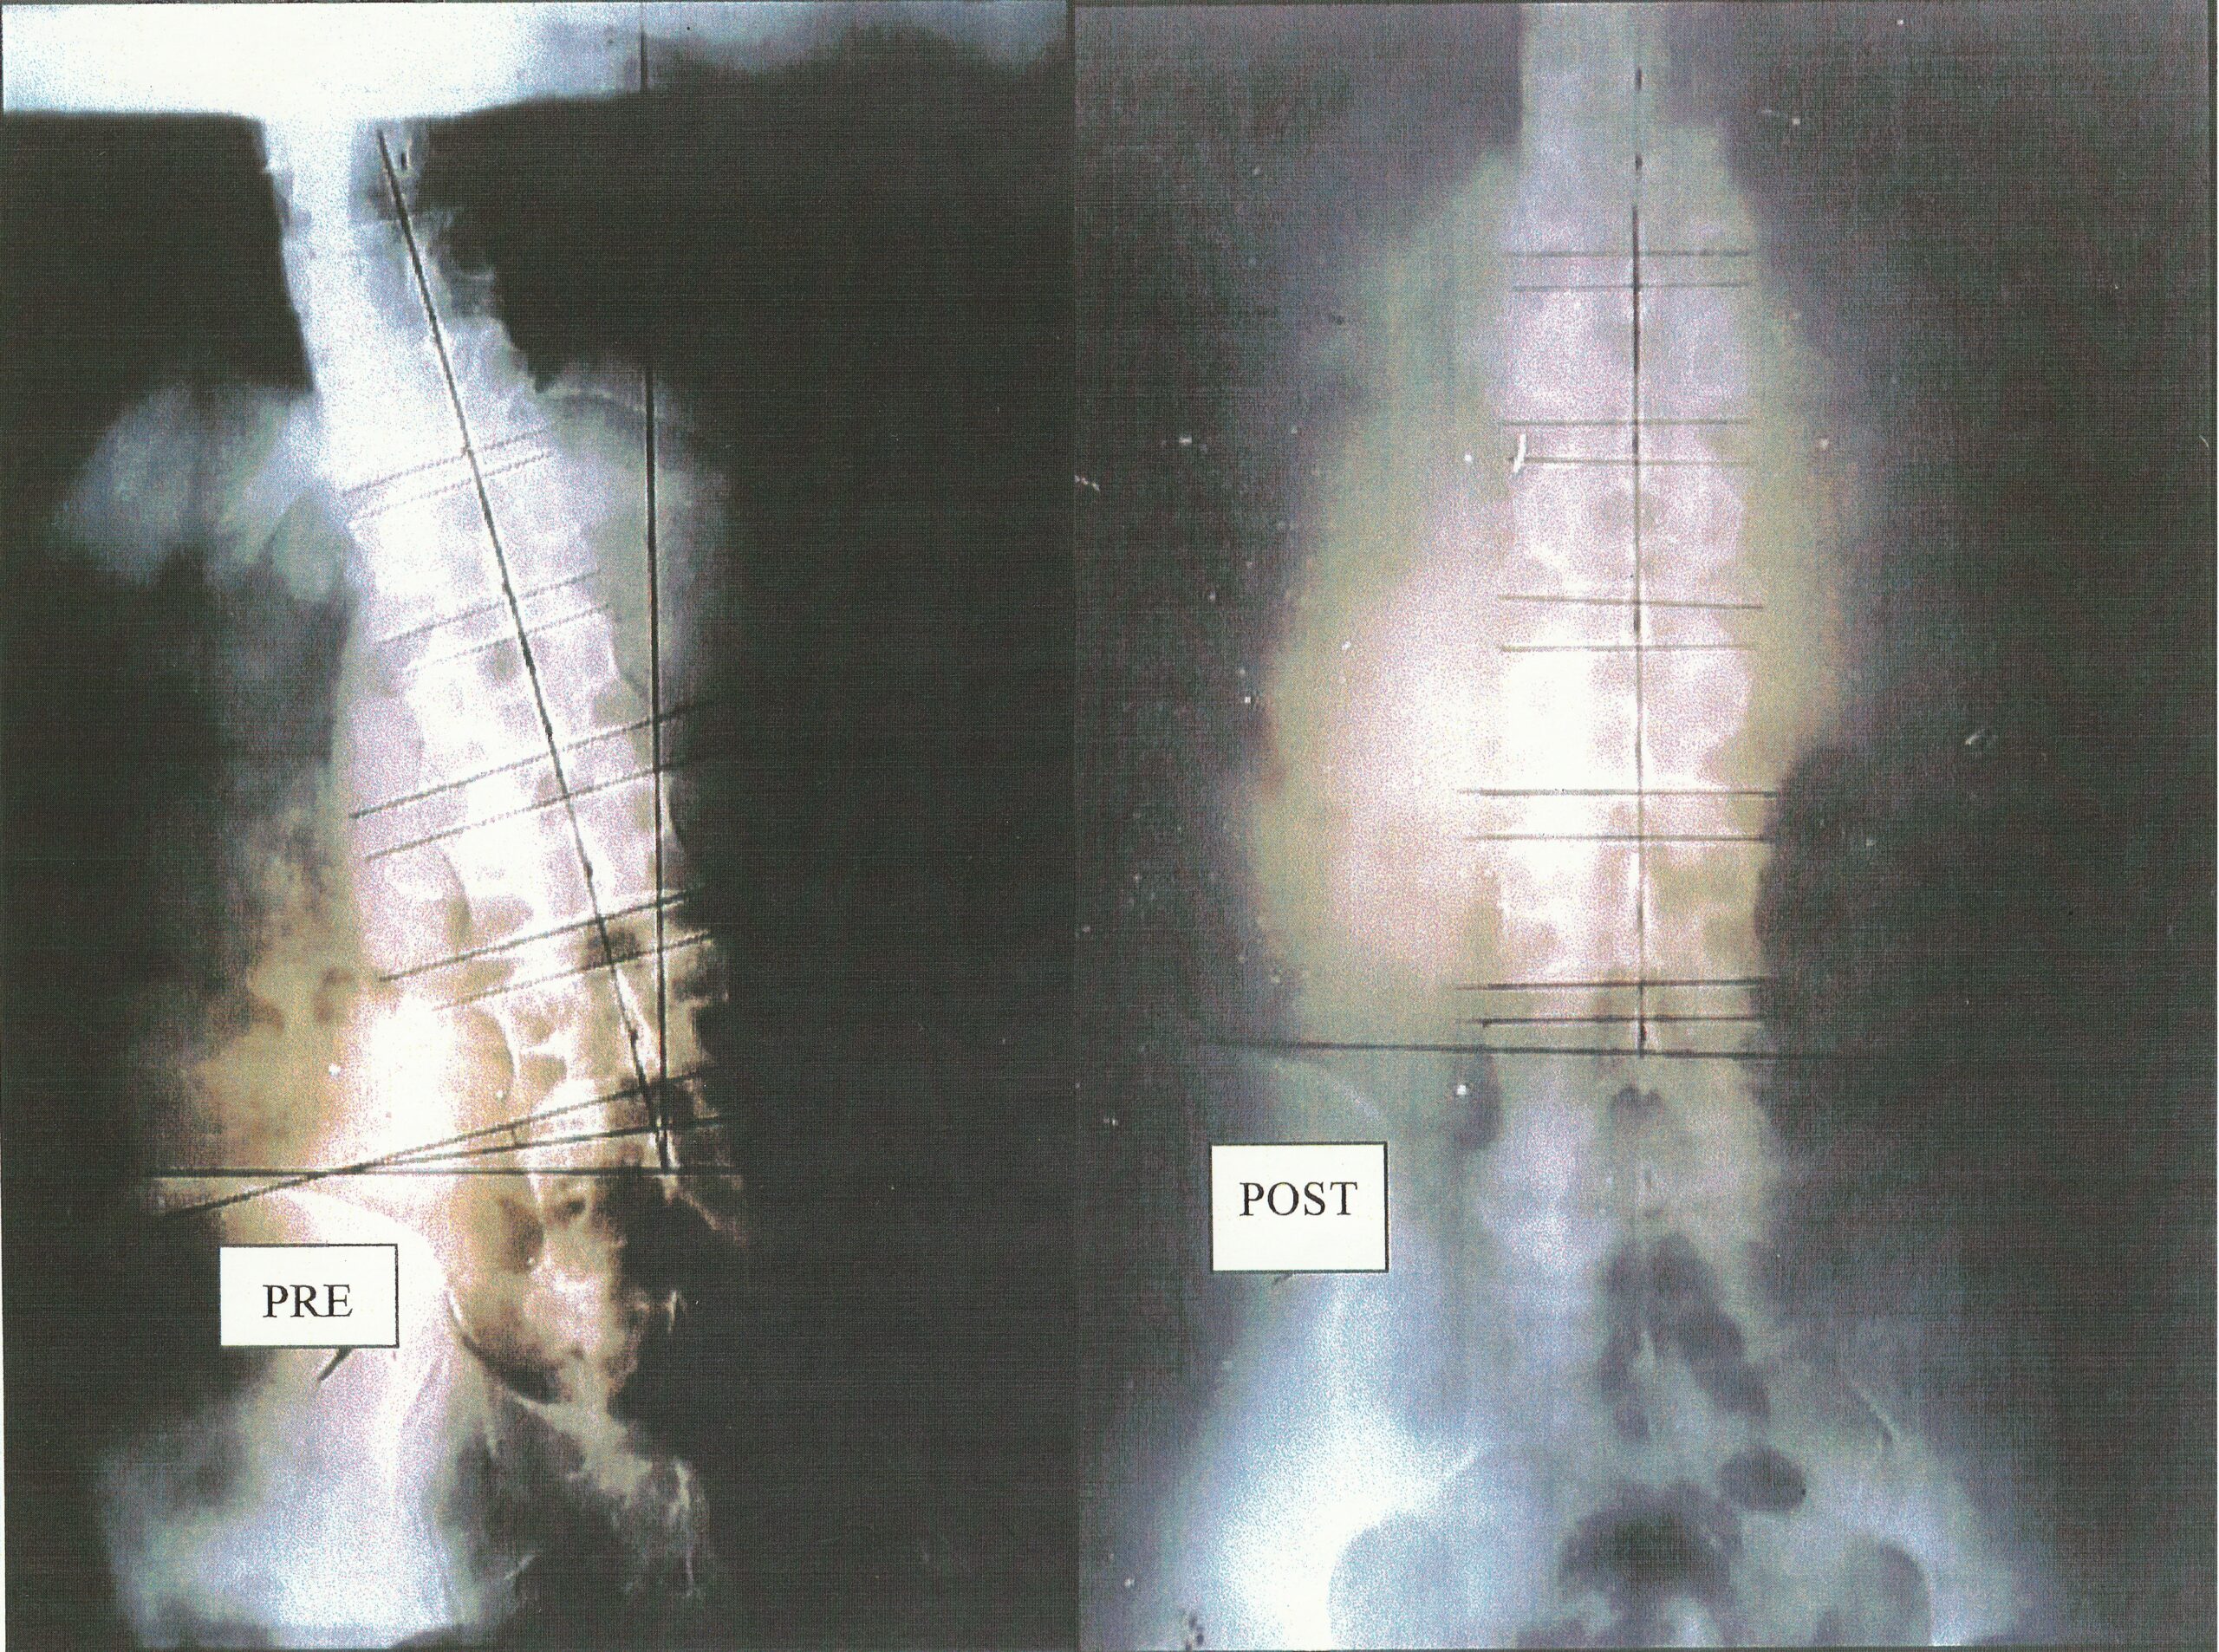

VISUAL EVIDENCE

科学的アプローチで見る施術の効果

右、施術後では傾いた重心がダイナミックに変化し、腰椎への負担が軽減したことがわかります。

短期間に大きな改善が期待できます。